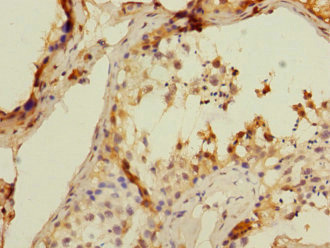

IHC (Immunohistochemistry), ELISA

Recombinant human T-cell surface glycoprotein CD8 beta chain protein (22-170AA)

Identifies cytotoxic/suppressor T-cells that interact with MHC class I bearing targets. CD8 is thought to play a role in the process of T-cell mediated killing.